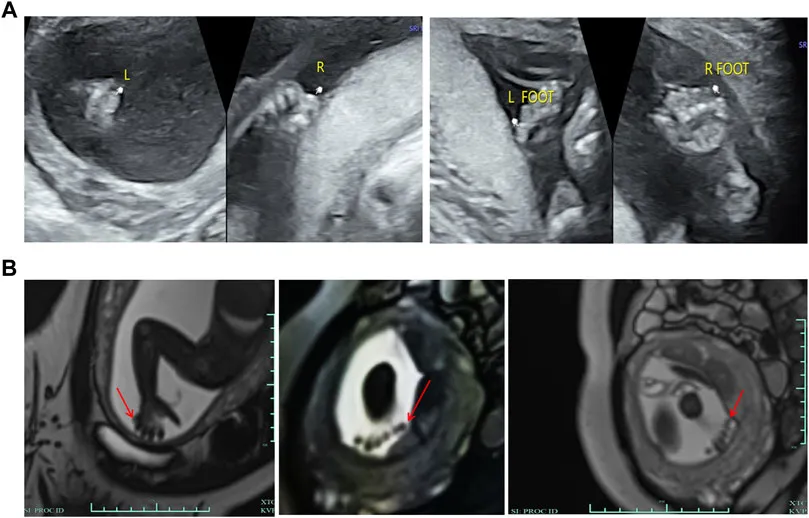

通过超声检查和MRI,研究团队首先确认了胎儿四肢存在PAP,额外的指(趾)大小约为0.6*0.4 cm,无明显骨性结构。随后的核型分析和CMA未发现任何染色体水平的异常。然而,Trio-WES揭示了SMO基因中存在复合杂合变异:c.1219C > G (p. Pro407Ala)和c.1619C > T (p. Ala540Val)。这两个变异分别来自母亲和父亲,Sanger测序进一步验证了这一发现,并证实了它们在家族中与疾病的共分离。

图3 胎儿的临床特征。 (A) 超声显示双脚小趾外侧和双手小指外侧有第六趾的回声,大小约为0.6*0.4厘米,其中没有明显的骨骼结构。 (B) MRI显示右手小指外侧有指状信号阴影,而左手手指数量因胎儿位置不清晰。双脚均可见六个趾状信号阴影。